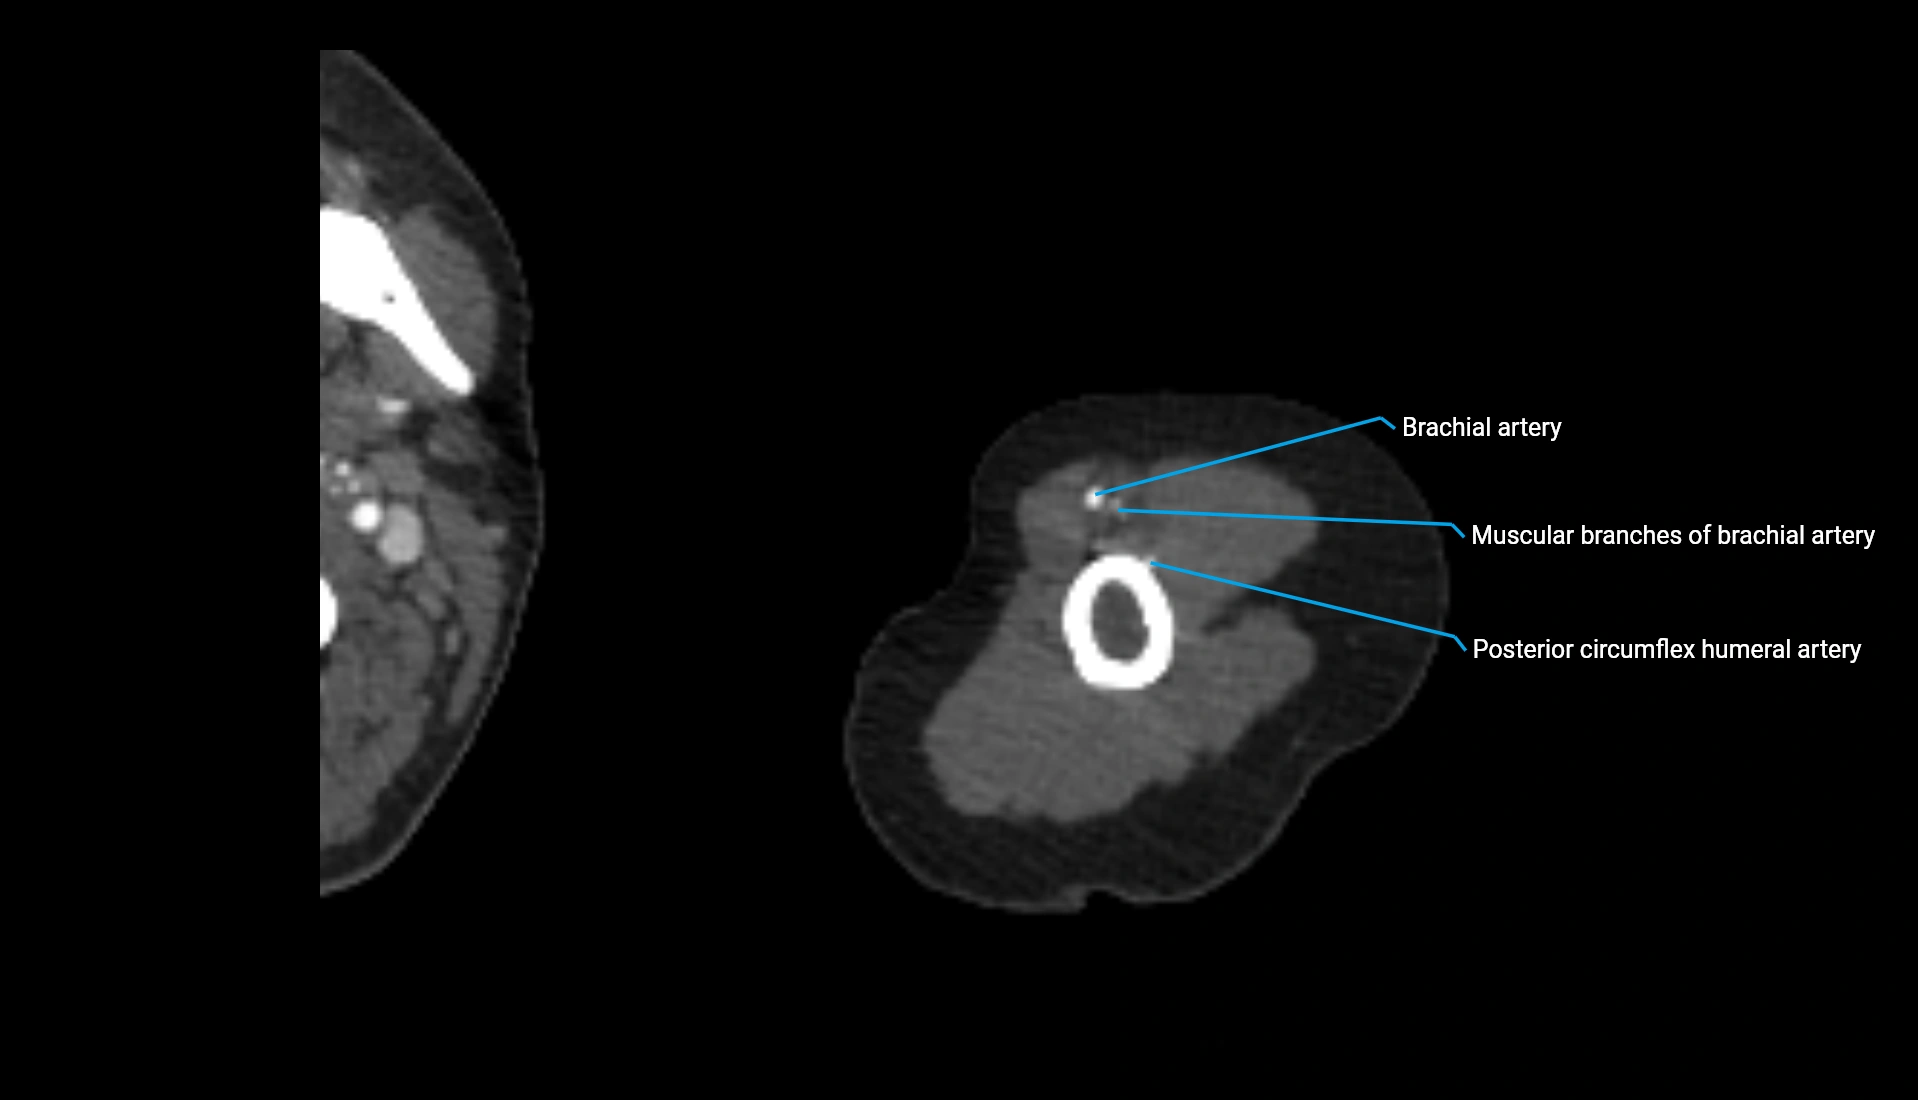

CT Appearance

Non-Contrast CT:

• Cortex: High-density, sharply defined

• Subchondral bone: Dense cancellous matrix

• Articular surface: Smooth concave contour articulating with the capitellum

• Excellent for evaluating bone integrity, alignment, and subtle fractures

Post-Contrast CT:

• Bone: No enhancement

• Joint capsule and synovium: Mild enhancement outlining the joint

• Improves contrast between soft tissues and bony margins

• Useful in detecting subtle joint abnormalities or postoperative changes